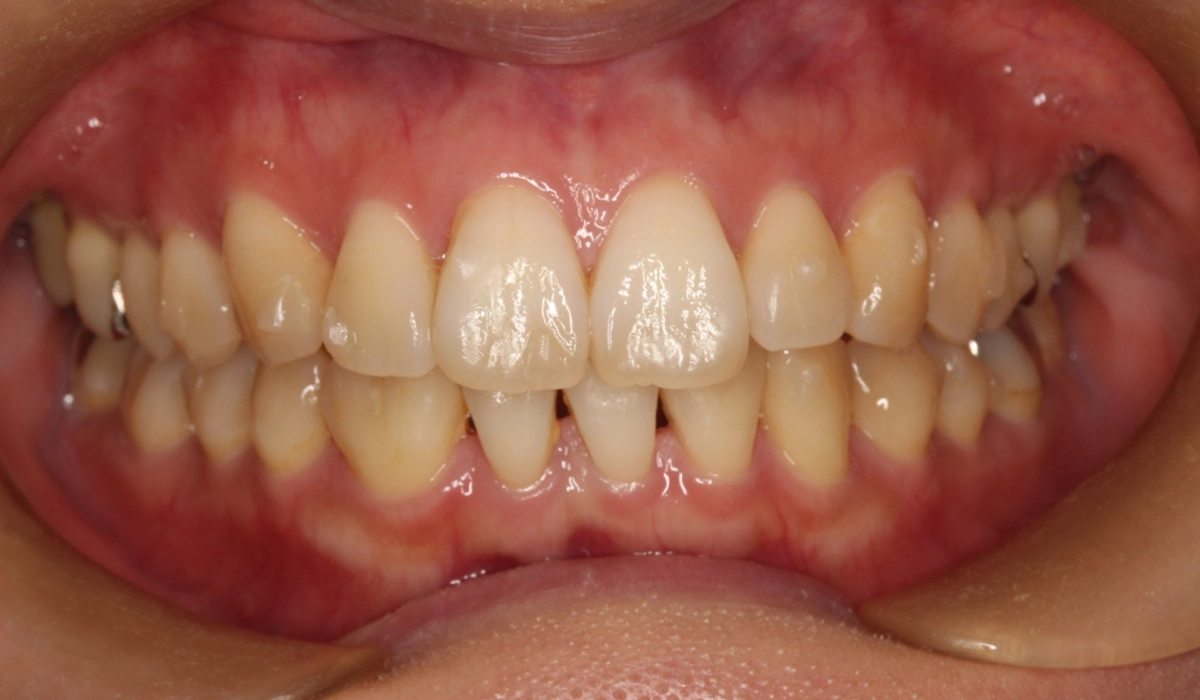

術前:正面

術後:正面